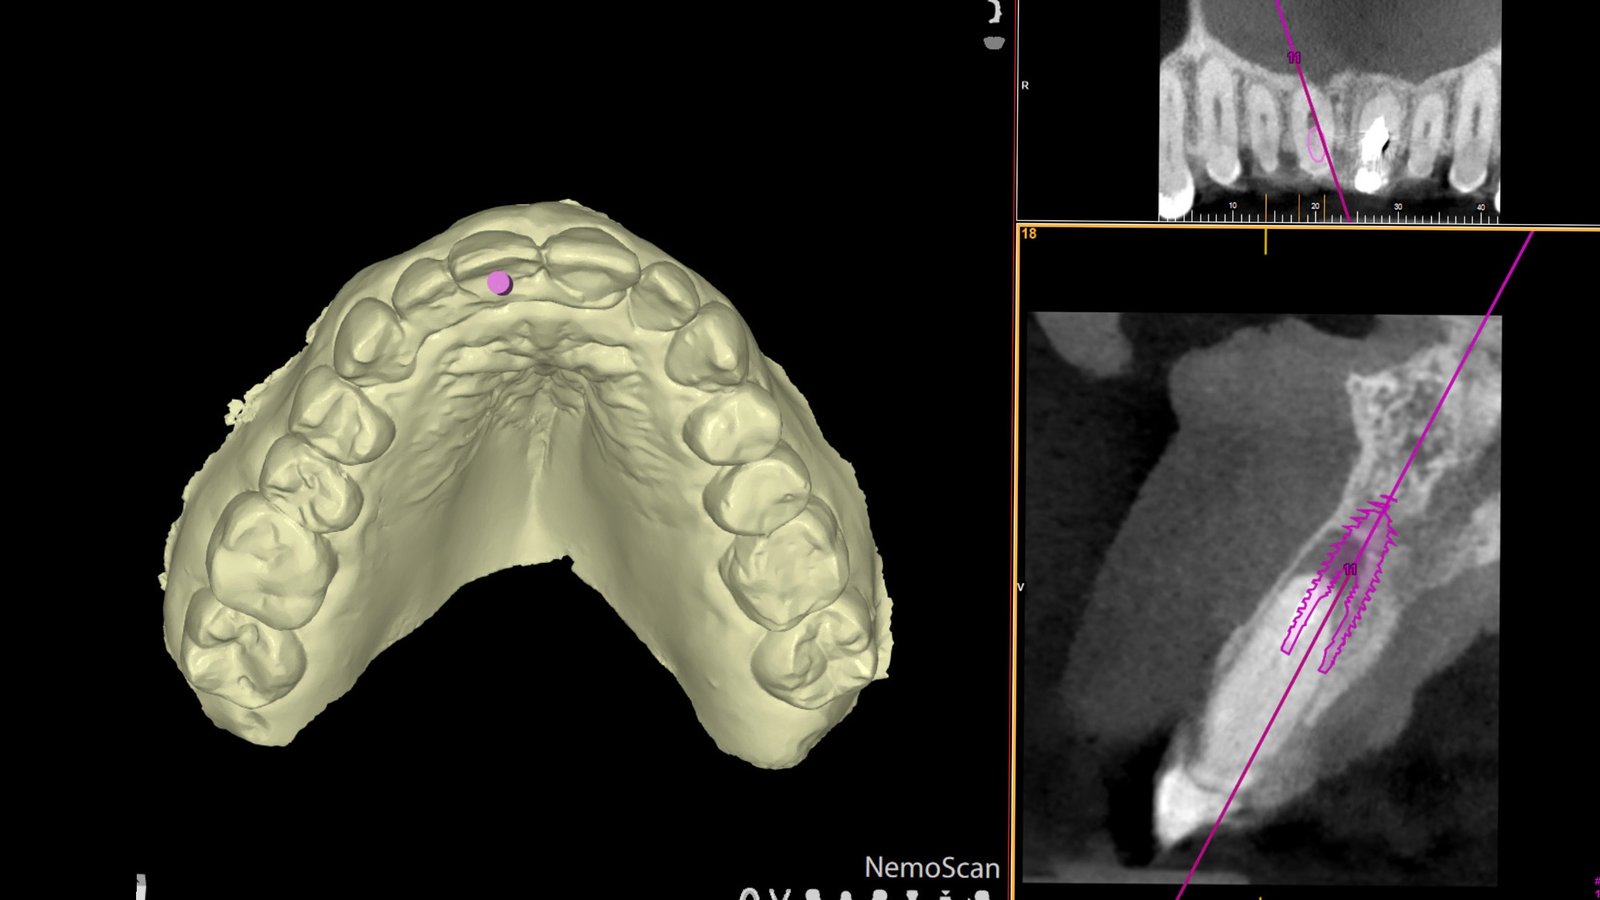

Planificamos cada caso con cirugía guiada digital para una colocación precisa y segura, reduciendo molestias y acelerando la recuperación.

1. Evaluación y planificación: estudio clínico, tomografía y diseño digital.

Planificación digital de implantes